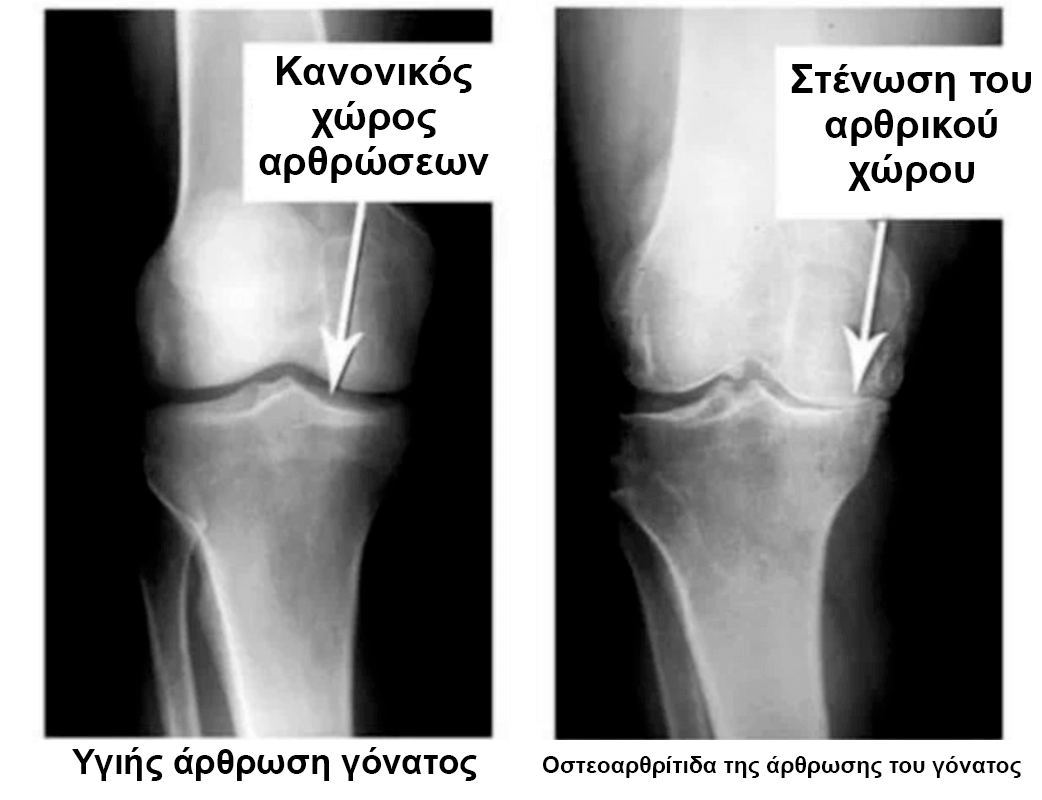

Κοιτάξτε αυτές τις εικόνες, θα δείτε ότι στη δεξιά εικόνα δεν υπάρχει χώρος στις αρθρώσεις, τα οστά τρίβονται μεταξύ τους και προκαλούν έντονο πόνο. Και αυτή η διαδικασία είναι πολύ δύσκολο να σταματήσει! Σε λίγα χρόνια ο άνθρωπος θα μίνει ανάπηρος και δεν θα μπορεί να συντηρηθεί μόνος του.